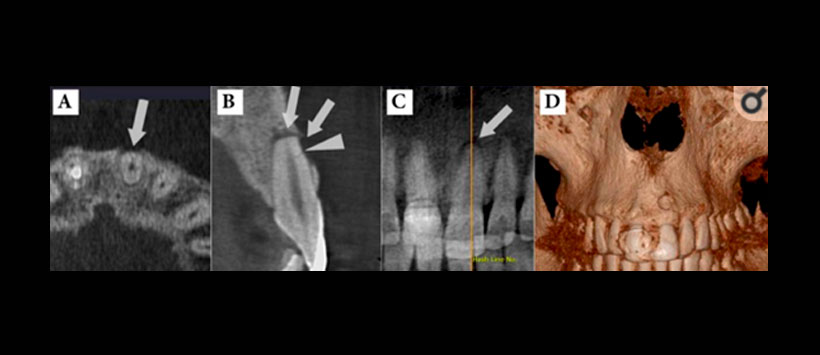

- Evaluacion de zonas pre quirurgicas – Figura 2